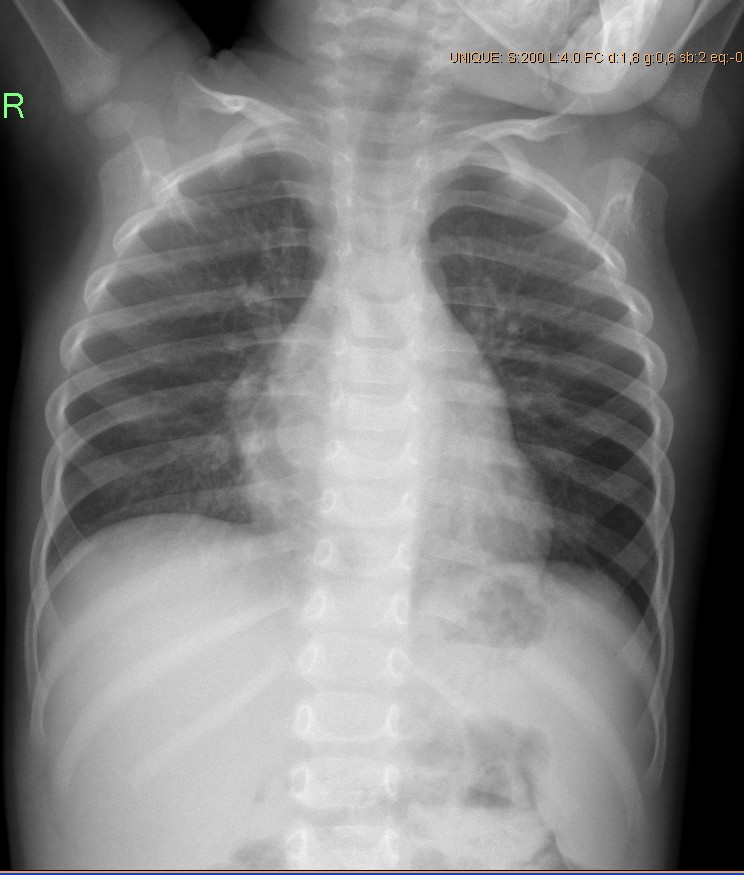

Снимок грудной клетки здорового ребенка: примеры и диагностика

Раздел: Мудрость в объективе